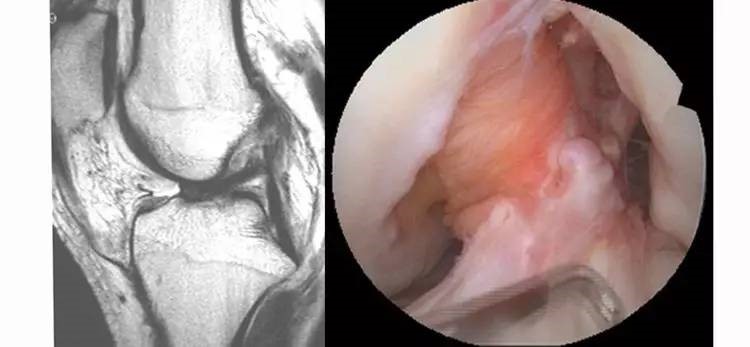

9.内侧半月板后角撕裂:内侧半月板后角是ACL的重要稳定结构,一旦发现青壮年患者的内侧半月板后角损伤,应该高度怀疑是ACL的继发损伤。常常见于陈旧损伤患者。

22.jpg

10.外侧半月板后根损伤:外侧半月板后根撕裂的受机制与ACL损伤的机制相似,因此发现外侧半月板后根损伤时必须考虑有ACL损伤的可能性。

23.jpg

11.半月板桶柄状撕裂:为膝关节的一种严重损伤,常伴有ACL损伤。

24.jpg